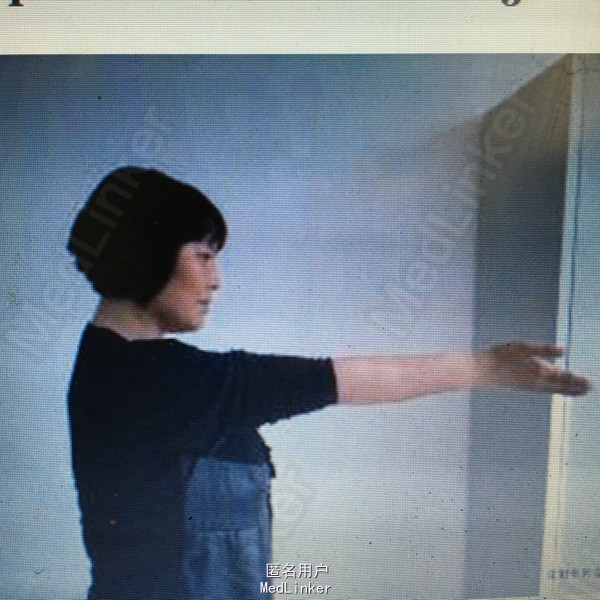

女性患者,43岁,因交通伤致右尺桡骨开放性骨折,当地医院行清创、骨折切开复位内固定术,术后尺侧切口反复红肿、流脓,经换药治疗4个月前臂仍疼痛、畸形、功能受限,X线片(A, B);第1阶段手术探查明确诊断(感染范围、程度及细菌种类),桡骨重新复位、内固定、恢复力线、间接稳定尺骨,尺骨骨折断端清创、抗生素骨水泥占位器置入(C),术后X线片(D, E);全身及局部应用敏感抗生素;第2阶段膜诱导技术修复骨缺损;切开诱导生成的生物膜,取出骨水泥占位器,钢板固定骨折(F, G);髋臼锉取骨技术获取粉碎松质骨、皮质骨混合颗粒,锁定钛板内固定和愈合片子(H, I)